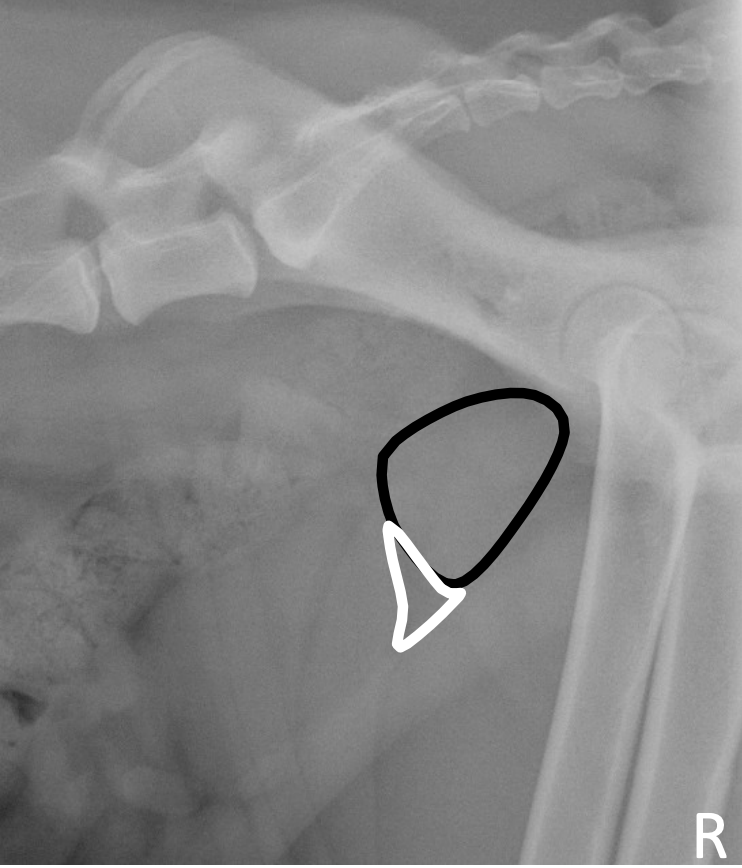

What is shown in this image?

A

normal prostate gland

-triangular fat pad present between bladder and prostate

*presence of triangular fat pad

-between ventral-caudal aspect of urinary bladder, cranio-ventral portion of prostate gland, and caudo-ventral abdominal wall